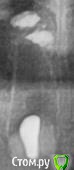

kamranchick Опубликовано 30 мая, 2018 Поделиться Опубликовано 30 мая, 2018 Реколы первые 1 Ссылка на комментарий

АнтонТЛТ Опубликовано 30 мая, 2018 Поделиться Опубликовано 30 мая, 2018 (изменено) Чет как-то не ахти. Как думаешь в чем причина? Пробки неподвижны? Изменено 30 мая, 2018 пользователем АнтонТЛТ Ссылка на комментарий

kamranchick Опубликовано 30 мая, 2018 Поделиться Опубликовано 30 мая, 2018 Чет как-то не ахти. Как думаешь в чем причина? Пробки неподвижны?Пробки намертво приклеены.Причина не знаю в чем(Это провал, ибо пациент готовится на имплантацию уже.Тут даже 3.5 с трудом проходит 1 Ссылка на комментарий